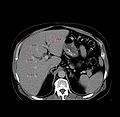

The workflow reads as follows [after segmentation]:

1. Export the segmentation to the planning program.

2. Run the planning program.

3. Load the plan specified in an xml file into Slicer for visualization and modification.

4. User can view the plan. Ablations are overlayed onto the image slices. Ablation locations are from the xml file and the size of the sphere is already available in Slicer before step 1.

5. User can move ablation locations.

6. Export the modified plan.